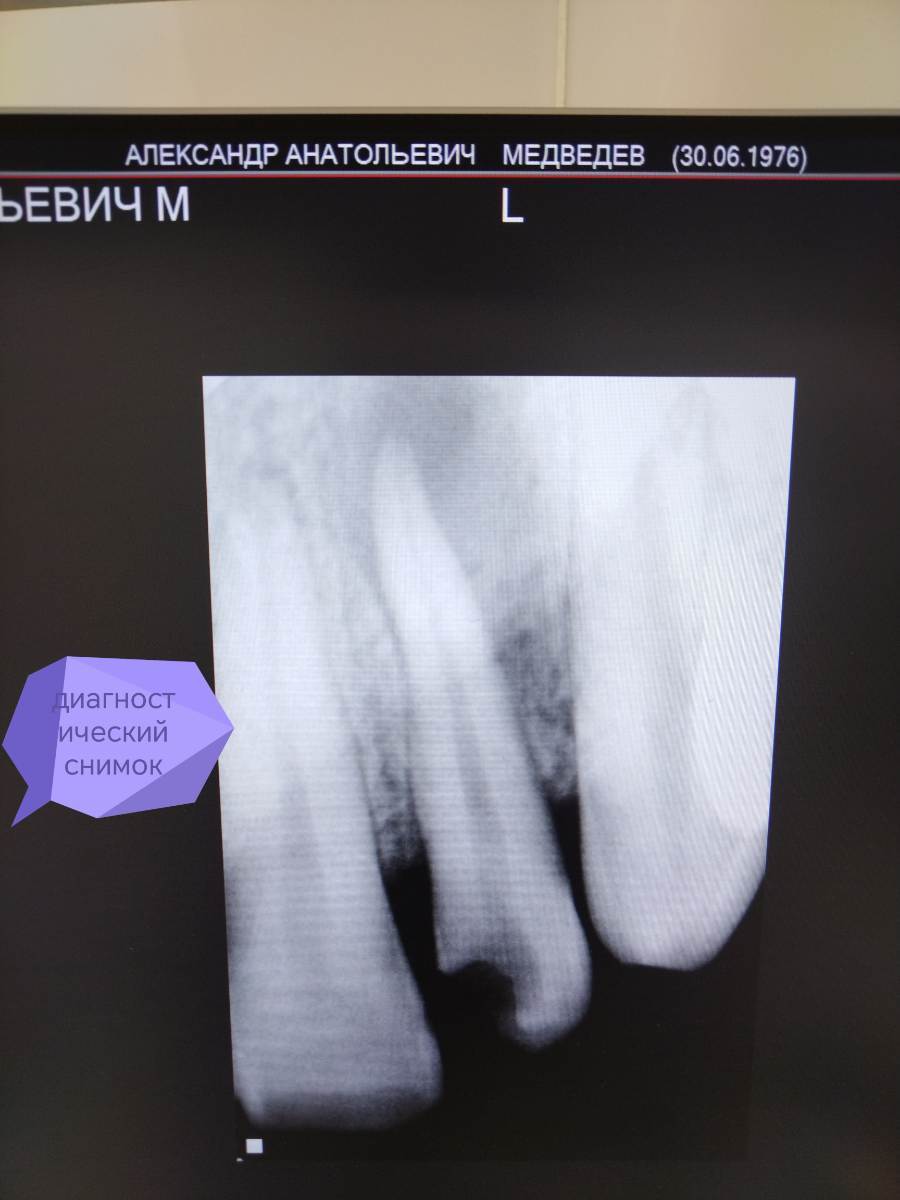

АВА2018 Опубликовано 28 декабря, 2025 Поделиться Опубликовано 28 декабря, 2025 Цитата Добрый вечер, коллеги 🙂Оцените, пожалуйста, качество пломбирования зуба 22 и есть ли перерасширение устьевой части канала.... Протокол работы: В 1 посещение-Механическая и медикаментозная обработка канала ручными к-файлами до 45 размера , промывание 3% раствором паркана, ЭДТА, активация эндоактиватором, вода. Изначальный размер канала 25 размер к -файла....Высушивание, получен экссудат в небольшом количестве. Временная пломбировка кальсептом на 2 недели. 2 посещение-Жалоб нет. Снятие пломбы, вымывание кальция из канала 3 % раствором паркана, водой дистиллированной. Долго не могла вымыть кальций из канала, при активации эндоактиватором выходили стружки кальция.... Постоянная пломбирование пастой Н+ с гуттаперчевыми штифтами методом латеральной конденсации. Пациенту придёт через 6 месяцев для контроля заживления.. Ссылка на комментарий

АВА2018 Опубликовано 28 декабря, 2025 Автор Поделиться Опубликовано 28 декабря, 2025 Скажите, пожалуйста, есть ли перерасширение цервикального дентина? Я работала без устьевика... Но на снимке отчётливо вижу перерасширение... Да и вообще проблема у меня с вымыванием кальция из каналов , я не могу понять, вымыла ли я его полностью, всё равно идёт белая стружка при активации. Я потом беру мастер-файл и н-файл по стенкам вожу и всё равно идёт белая стружка... Есть вообще ощущение, что я каналы перерасширяю.... Фанатизм мой до добра не доведёт... 😩Переживаю ща пациента.... Ну вот это перерасширение или просто ракурс такой? Ссылка на комментарий

Carioznik Опубликовано 29 декабря, 2025 Поделиться Опубликовано 29 декабря, 2025 9 часов назад, АВА2018 сказал: Но на снимке отчётливо вижу перерасширение... а в реальности ? Возможно, просто ракурс такой 9 часов назад, АВА2018 сказал: вымывание кальция из канала 3 % раствором паркана, кроме гипохлорита , еще ЭДТА добавляйте, он еще и кальций поможет убрать. 9 часов назад, АВА2018 сказал: потом беру мастер-файл и н-файл по стенкам вожу и всё равно идёт белая стружка. Возможно, это больше стружка дентина, а не кальций? С Н файлом поосторожнее, он очень агрессивный, да и смысла особого в нём нет. 9 часов назад, АВА2018 сказал: Долго не могла вымыть кальций из канала, при активации эндоактиватором Попробуйте активацию ультразвуком. Есть ещё щёточка для активации и очистки: G-brush. 1 Ссылка на комментарий

Carioznik Опубликовано 30 декабря, 2025 Поделиться Опубликовано 30 декабря, 2025 В 29.12.2025 в 00:11, АВА2018 сказал: обработка канала ручными к-файлами до 45 В 29.12.2025 в 00:15, АВА2018 сказал: работала без устьевика Еще забы написать: При такой инструментальной обработке - не должно быть перересширения. Если только H-файлом "наскребли" (но это уж надо сильно постараться). Скорее всего анатомия изначально такая+ ракурс еще возможно.... По кальцию - да, вымывать его не просто, но УЗ - хорошо справляется с этим. Просто эндоактиватором, да,. плохо отмывается и долго Ps: с Наступающим! 1 Ссылка на комментарий